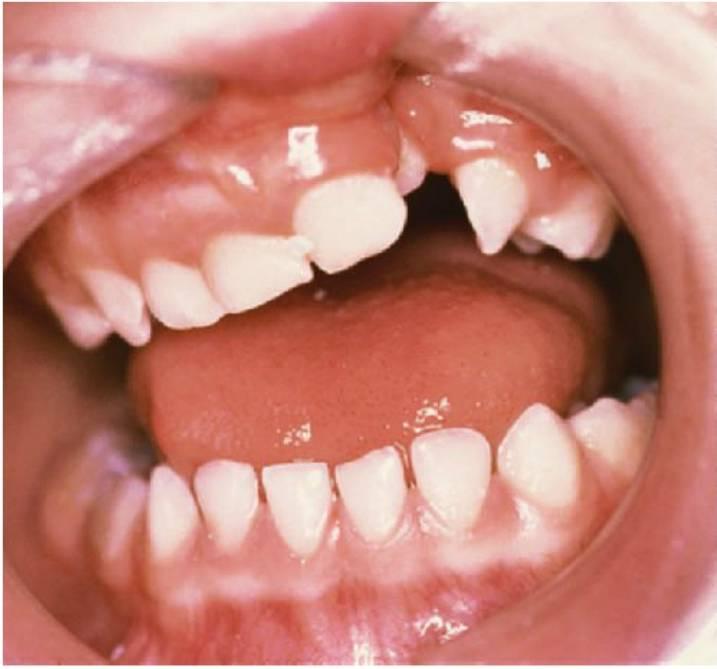

Las hendiduras labiales y palatinas completas pueden requerir un tratamiento ortodóncico extenso que se debe realizar, en algunos casos, poco después del nacimiento y hasta la madurez física.

Con frecuencia, la primera referencia al ortodoncista se hace a los 8 años de edad, a menos que se haya visto al niño en la etapa de bebé para la ortopedia prequirúrgica, en cuyo caso se le puede examinar tomando los datos dentales pediátricos como referencia. El paciente se remitirá más temprano al ortodoncista en ciertos casos en los que se presente mordida cruzada de un incisivo u otros problemas de relación entre los incisivos, alrededor de los 7 años de edad, para la corrección de dichos problemas; sin embargo, en la mayoría de los casos, el trata miento simple que se aplica se desarrolla en el ámbito del cuidado dental pediátrico normal (expansión palatina). El tratamiento ortodóncico en su caso puede dividirse en tres etapas.

El tratamiento puede implicar (fig. 12.6):

- Tratamiento interceptivo, como la alineación mínima de los dientes para facilitar la alineación anterior.

- Expansión palatina previa al injerto óseo alveolar, que puede significar un tratamiento bastante corto con aparatología fija para obtener la forma óptima de la arcada o mejorar el acceso para la cirugía y que comienza unos 12 meses antes de cualquier injerto óseo alveolar. En general, el injerto se coloca cuando el lado de la hendidura del canino permanente muestra entre uno y dos tercios de desarrollo radicular (fig. 12.7). No obstante, el aparato se mantiene durante los 4-6 meses posteriores al injerto para proporcionar estabilidad y transcurrido este tiempo puede sustituirse por un retenedor pasivo.

- Aparatos ortopédicos dentofaciales para niños con un desarrollo mandibular ostensiblemente anómalo.